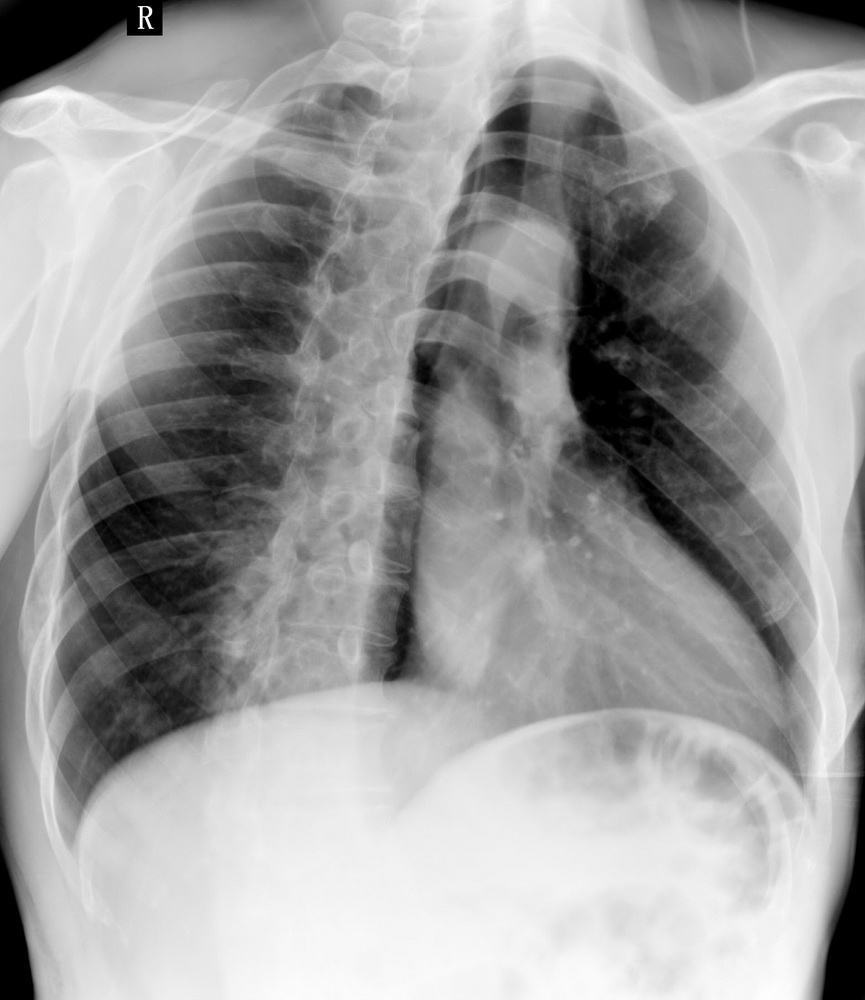

患者,男性,41y,外伤病号,来拍片,发现右侧第9后肋,肋骨膨大,有密度不均,想问大家,是否有问题,要考虑什么东西,谢谢

右侧第九后肋骨纤维结构不良。

考虑骨纤维异常增殖症(混合型)。

肋骨是骨纤好发部位。